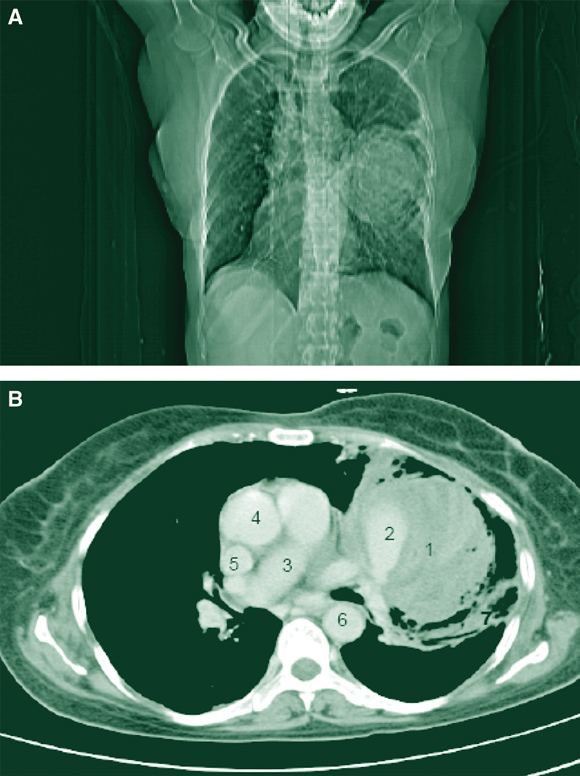

Pulmonary artery aneurysm